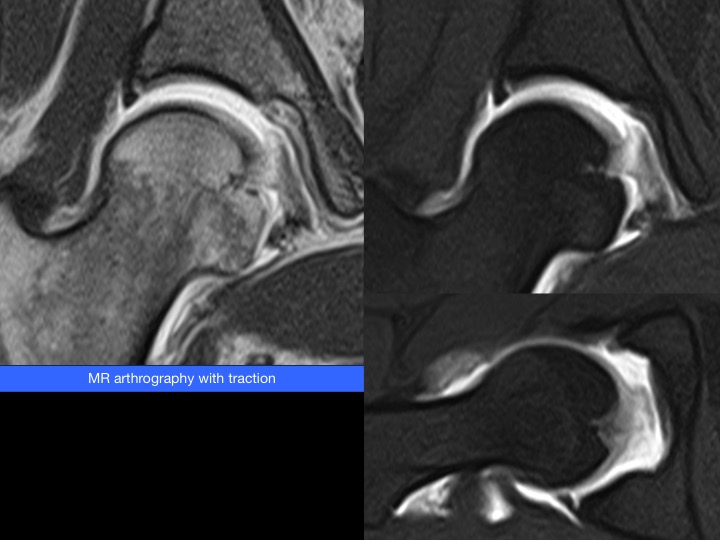

30-year-old woman runner with chronic groin pain. Hip instability on clinical examination.

Complete chronic ligamentum teres tear and hip instability. Complete tear of the ligamentum teres in the perifoveal region and increased articular distraction on MR-arthrography with leg traction system (8 Kg). Note also a small partial chondrolabral detachment. The patient was initially arthroscopically treated (ligamentum teres debridement and capsular plication) without clinical improvement. One year before an arthroscopically ligamentum teres reconstruction was performed (fascia lata graft).

This technique remains experimental and is limited to patients with high demands and persistent hip instability after conventional arthroscopic treatment. Reference article.